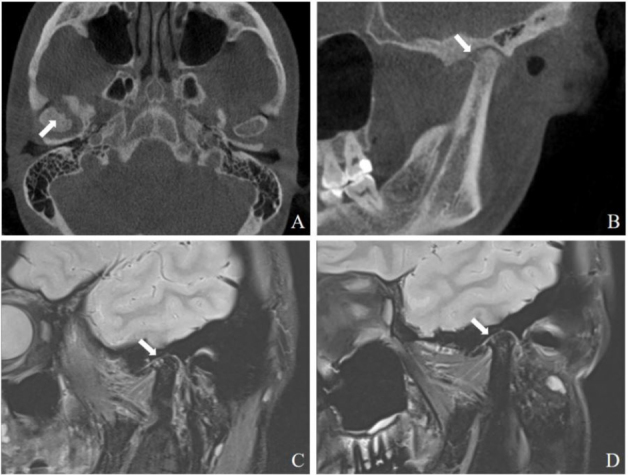

"Bouncing temporomandibular joint": Multiple temporomandibular lesions in a patient with rheumatoid arthritis.